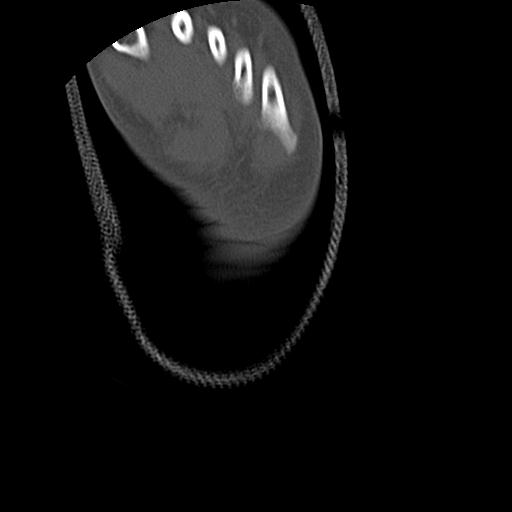

102766 1/5 1/12 左手関節 4R 28歳男性 左橈骨遠位端

102739 12/30 1/5 左手関節 4R 92歳女性 橈骨遠位端